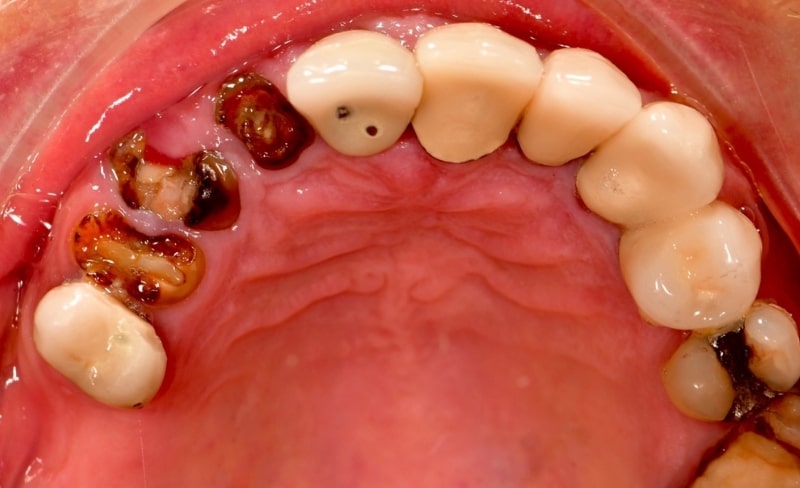

Upper and lower all-on-4 dental implants to restore function and aesthetics.